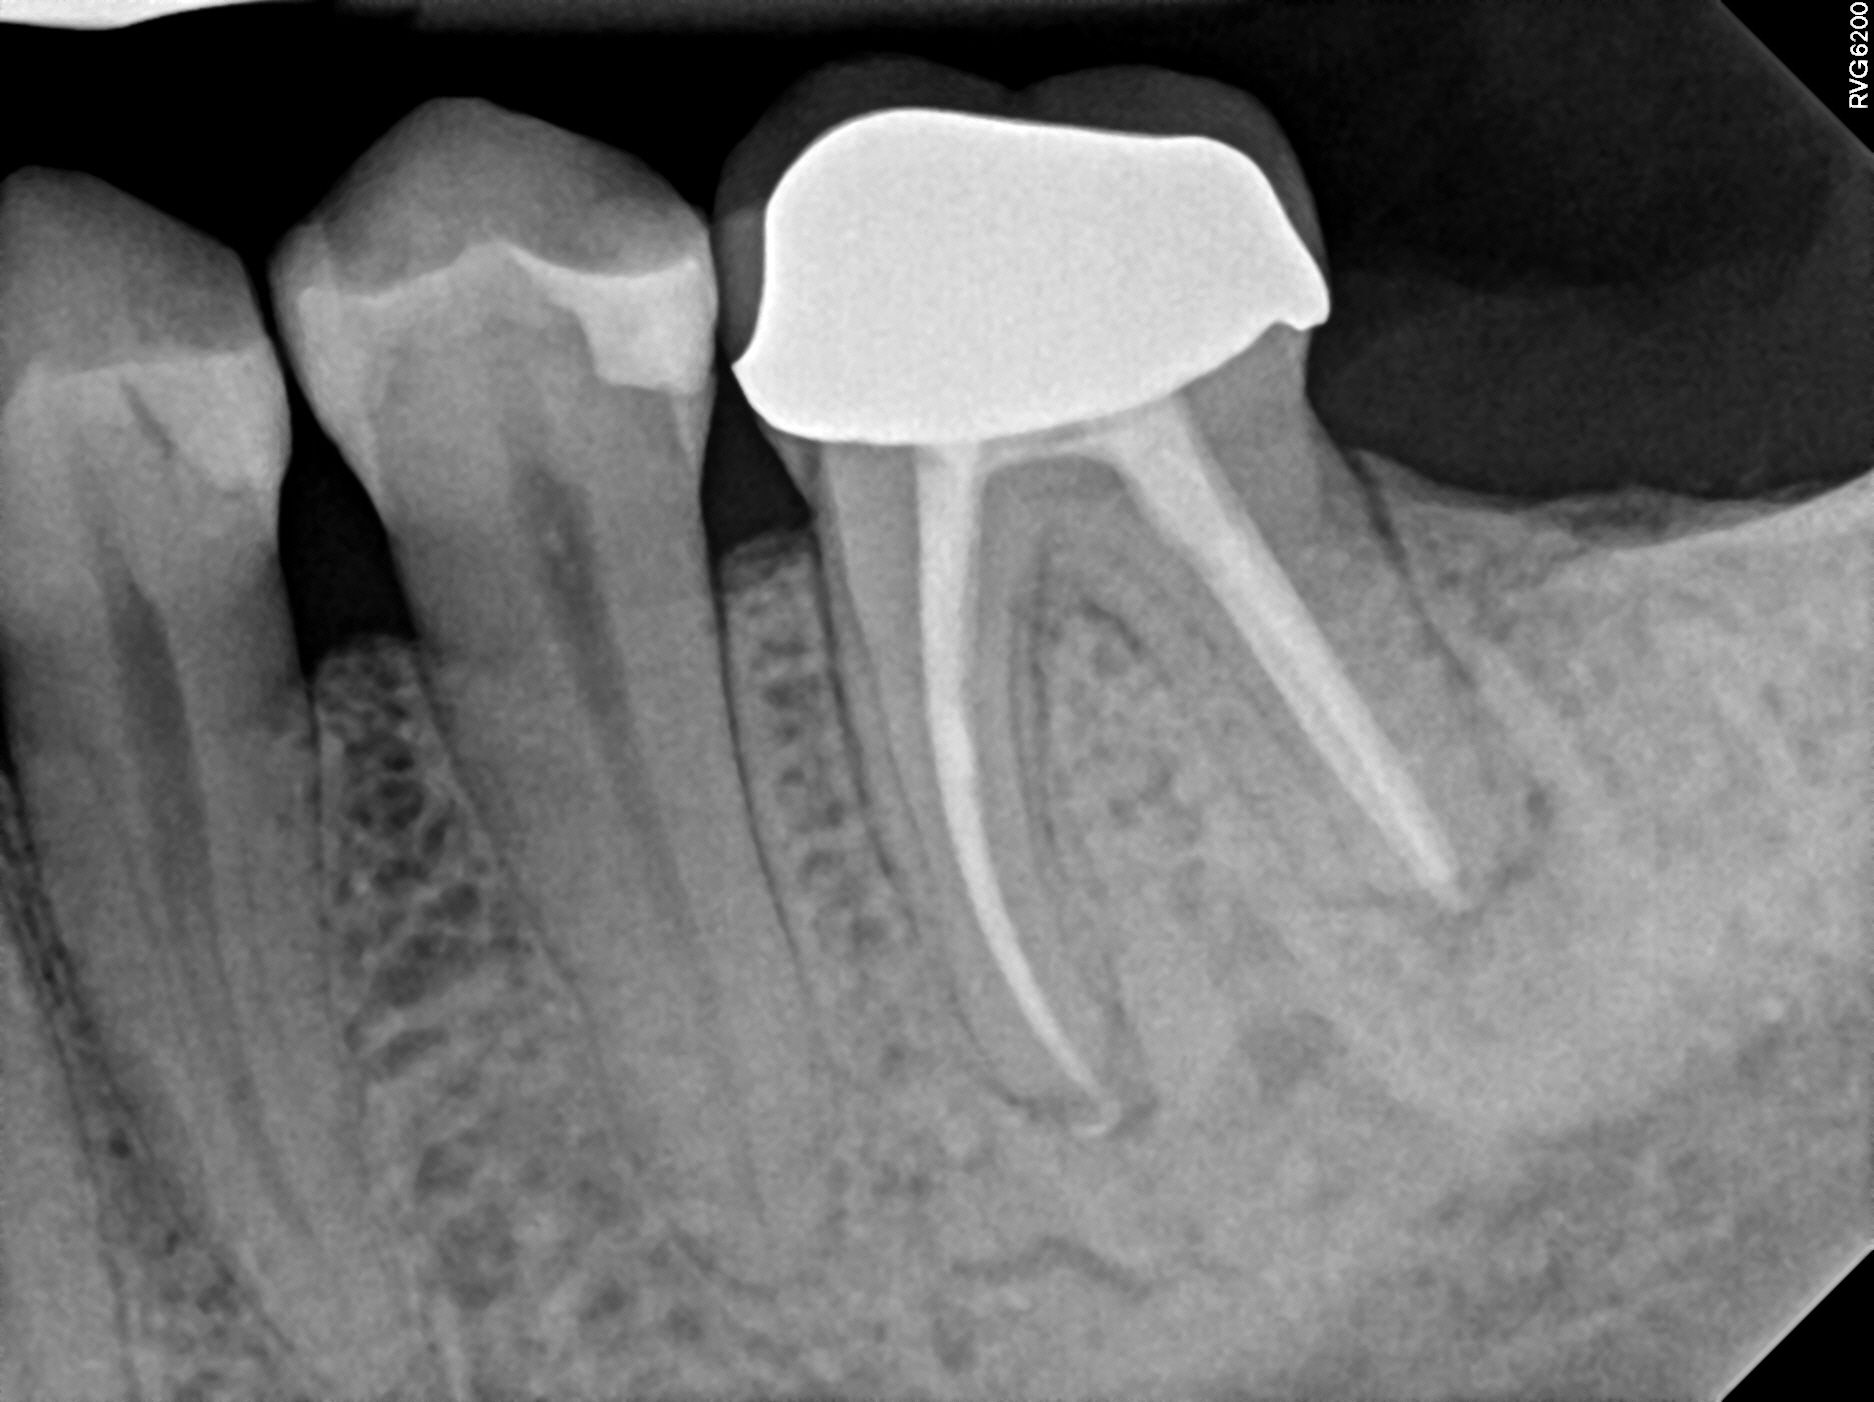

Case 2

This is a retreatment case. The picture on the left shows a lower molar that had been root canal treated many years prior, but either did not heal or at some point afterward became re-infected. The lesion is quite large, extending to the inferior alveolar nerve. While retreating the case Dr Cottle found a previously missed nerve canal (three in one root, five total in this one molar) and was able to disinfect all the canals again. The image on the right shows the completely healed bone one year later.